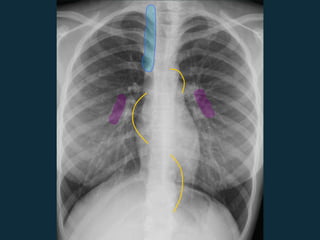

Linfadenopatia (LAN)  TermosEspecificos : • Alargamento Mediastinal • Alargamento Hilar  Evite usar termos como: • Hilo proeminente É importante conhecer o aspecto “normal” para reconhecer o que for “ anormal”

 Janela hilar inferior(hilar direita e/ou subcarinal)  Hilar esquerda  Subcarinal Linfoadenopatia